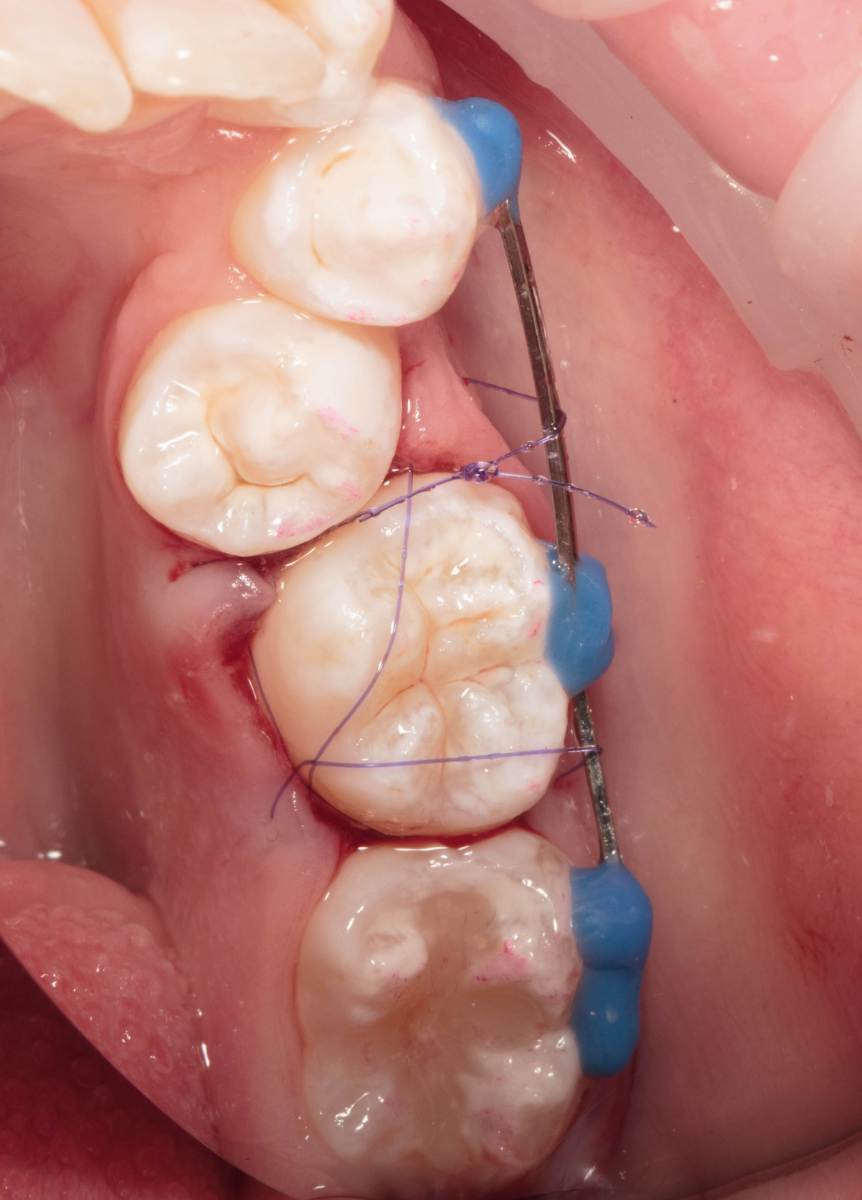

Женька Опубликовано 28 ноября, 2025 Поделиться Опубликовано 28 ноября, 2025 Всем привет, коллеги! 14 лет, терапевты ставят трещину по КТ (снимков до, к сожалению нет, косяк, каюсь). чуть сепарировав зуб и глянув на зуб под отлетевшим куском пломбы трещина "подтвердилась". Кейс на фото. Из интересного - маленький реколл в 1.5 года и спокойное перемещение зуба брекетами! 4 1 2 Ссылка на комментарий

Женька Опубликовано 17 декабря, 2025 Автор Поделиться Опубликовано 17 декабря, 2025 @сирена вот и завтра наступило) прощу прощения, что так долго, всё из головы вылетало на работе посмотреть. Пересадили в конце мая, к ортодонтии подключили в начале сентября ~3.5 месяца прошло с пересадки на тот момент. 1 Ссылка на комментарий